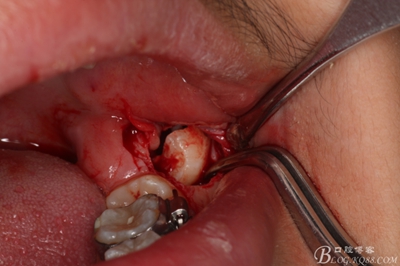

圖1.術(shù)前患者的全景片檢查:38、48牙冠已經(jīng)形成,牙冠方向為水平位,37、38近中位萌出。